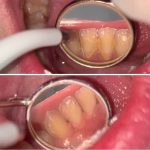

– Aici pacienții pot beneficia de: detartraj, igienizare cu airflow, iar pe viitor pot beneficia de un tratament dentar complet.

– Aici pacienții pot beneficia de: detartraj, igienizare cu airflow, testare HPV, consult oncologic preventiv, iar pe viitor pot beneficia de un plan de tratament dentar complet.

– Aici pacienții pot beneficia de: detartraj, igienizare cu airflow, consult ortodontic de specialitate, iar pe viitor pot beneficia de tratament dentar complet.

Evenimentul anterior in imagini